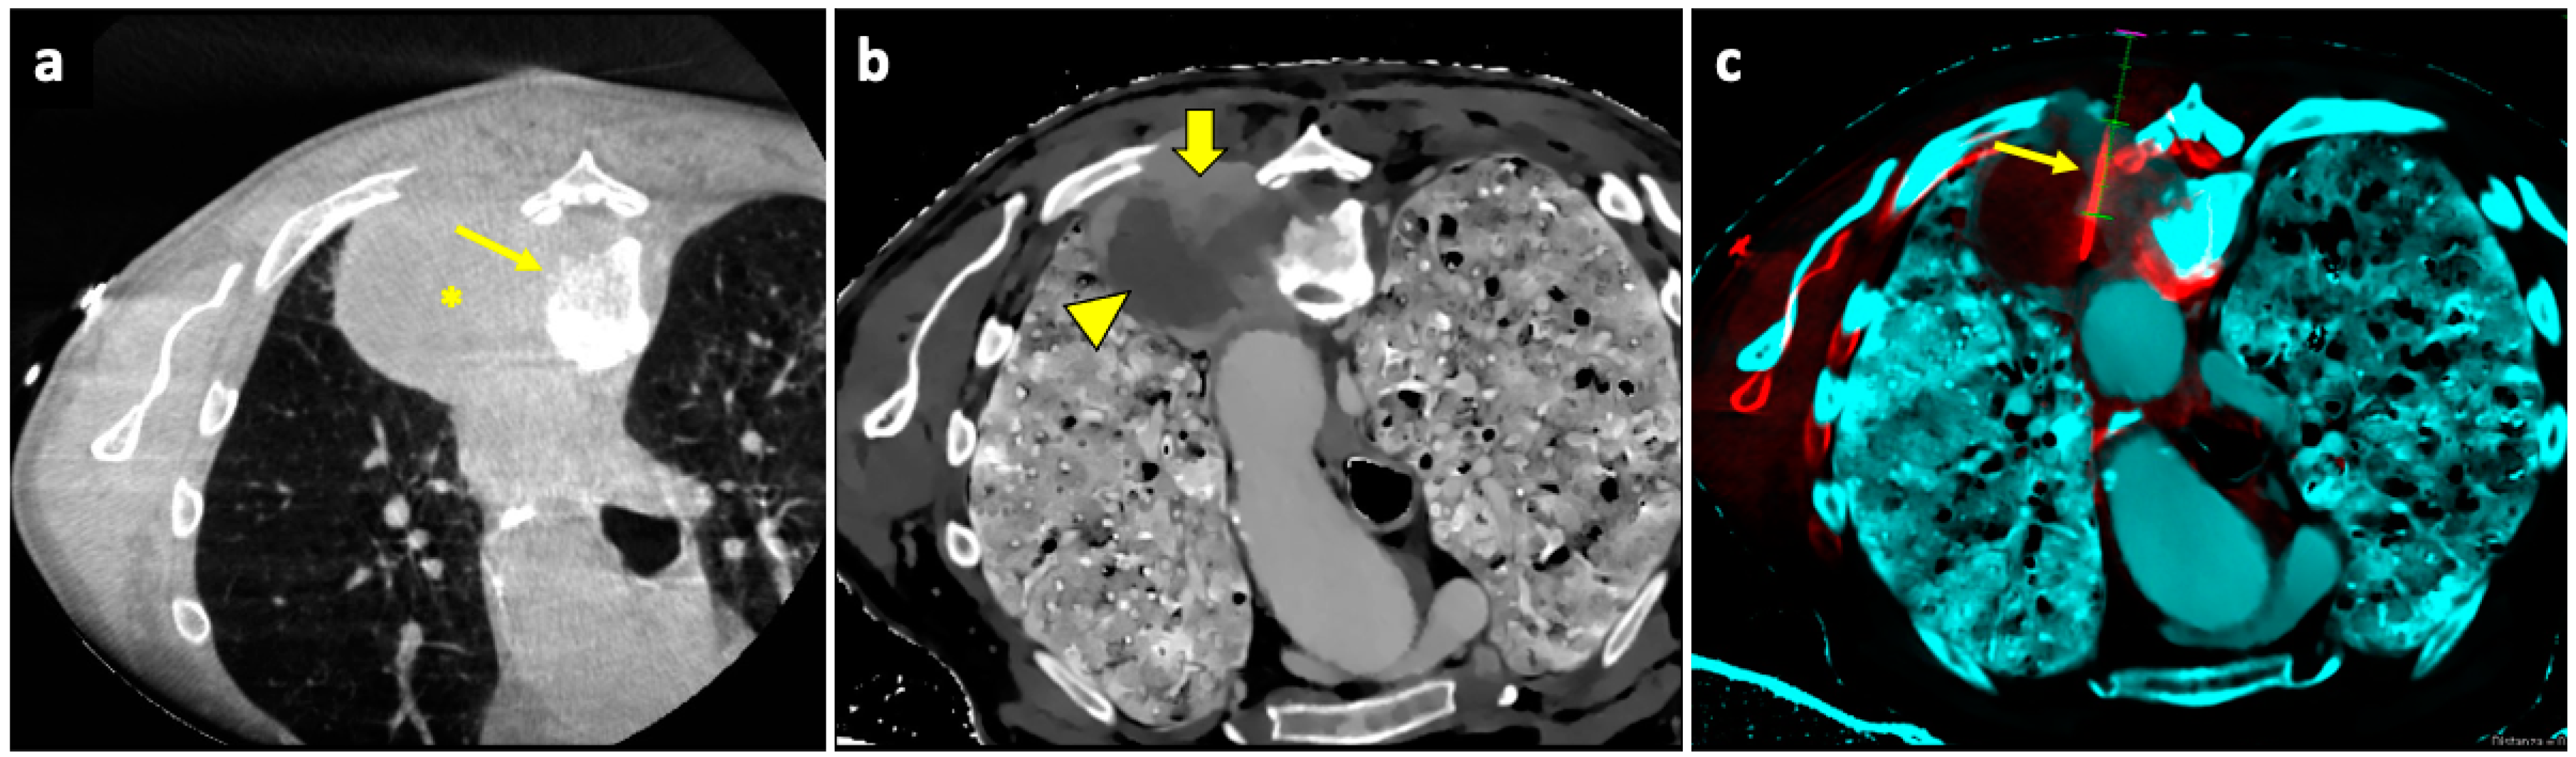

The CBCT system consists of flat-panel fluoroscopy and a CBCT scanner. The execution of CBCT-virtual-navigation-guided lung biopsy is performed in steps. The first step is to acquire a CBCT scan for adequate planning of the biopsy. Briefly, using the software (various software exist, by different vendors), the operator establishes the target lesion and the needle entry point at the skin surface, after which a virtual segment connecting the entry and target points is shown, representing the needle path. On the basis of this planning, the software automatically calculates the correct C-arm position to display the needle entry point on the patient’s skin. This phase of the procedure is called “entry point positioning”. After skin disinfection of the access area, under fluoroscopic guidance, the operator positions the needle tip at the cutaneous entry point, based on the CBCT image appearing on the monitor as a fusion of the 3D volume previously acquired using CBCT and the real-time fluoroscopy bidimensional plane. At this time, the C-arm rotates in the “progression view” position, perpendicular to the previous one. Then, the needle is advanced into the chest to reach the target point, following the virtual path previously determined and displayed on the monitor in real-time fluoroscopy. Then, a second CBCT scan is performed to verify the needle’s correct placement, and the biopsy is taken. A final scan is acquired to assess any complications [124]. An example of CBCT-guided biopsy is illustrated in Figure 4.

A useful technique in this setting is fusion imaging, which is defined as the process of overlapping imaging datasets from different modalities into a single composite imaging dataset. By using dedicated software, it is possible to overlap pre-procedural 18F-FDG PET/CT images to intra-procedural CBCT images, thus integrating functional and anatomical data, and to guide the needle towards the viable and metabolically active portion of the target lesion. An example of a biopsy guided by fusion imaging between CBCT and PET-CT is illustrated in Figure 5.